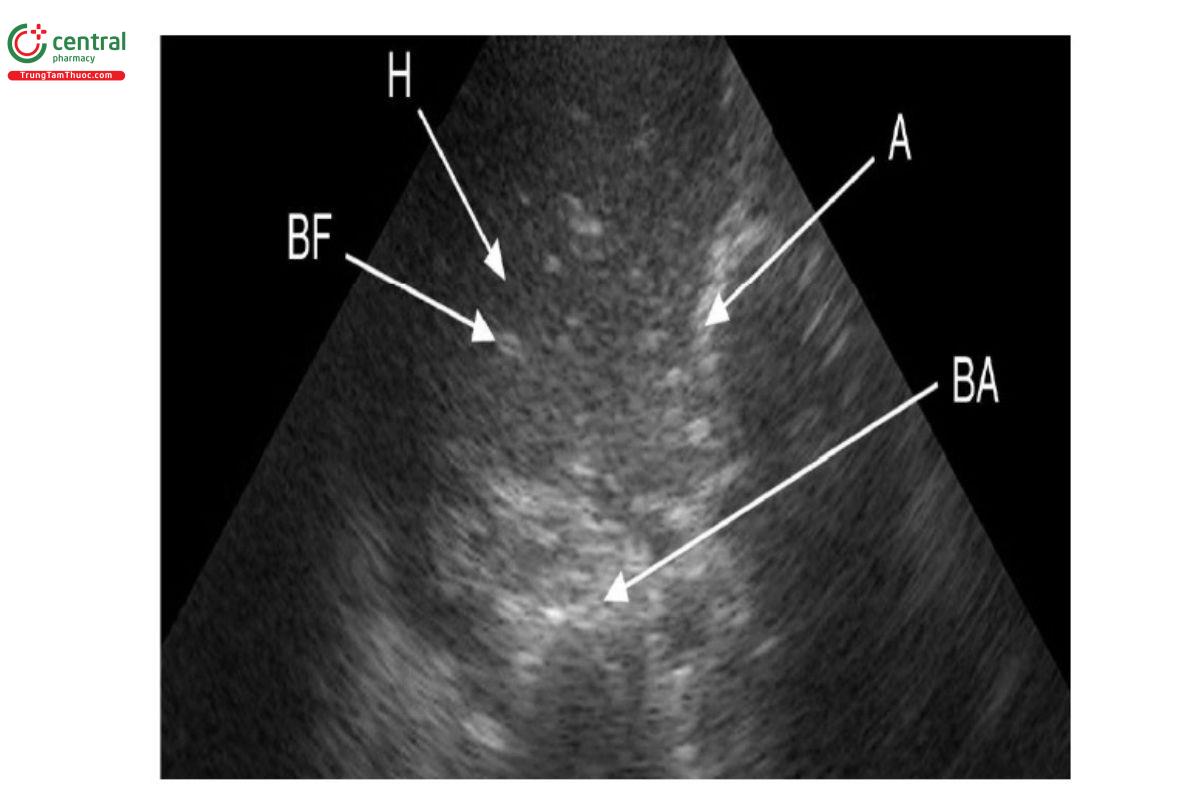

Dấu hiệu đông đặc phổi: Là vùng giảm âm chủ yếu dưới màng phổi hoặc vùng giảm âm có mật độ giống gan. Hình ảnh đông đặc trong viêm phổi thường có ranh giới không đều, không tròn. Khi có sự đông đặc dưới màng phổi, đường màng phổi không rõ ràng và sự trượt màng phổi giảm hoặc không có. Đông đặc có thể kèm dấu hiệu phế quản hơi (biểu hiện bằng các điểm tăng âm và/hoặc hình ảnh đường), giúp phân biệt với xẹp phổi [25, 32].

Chú thích: H: hepatization (gan hóa); A: atelectasis (xẹp phổi); BF: fluid bronchogram (dấu hiệu phế quản chứa dịch); BA: aerial bronchogram (dấu hiệu phế quản hơi)